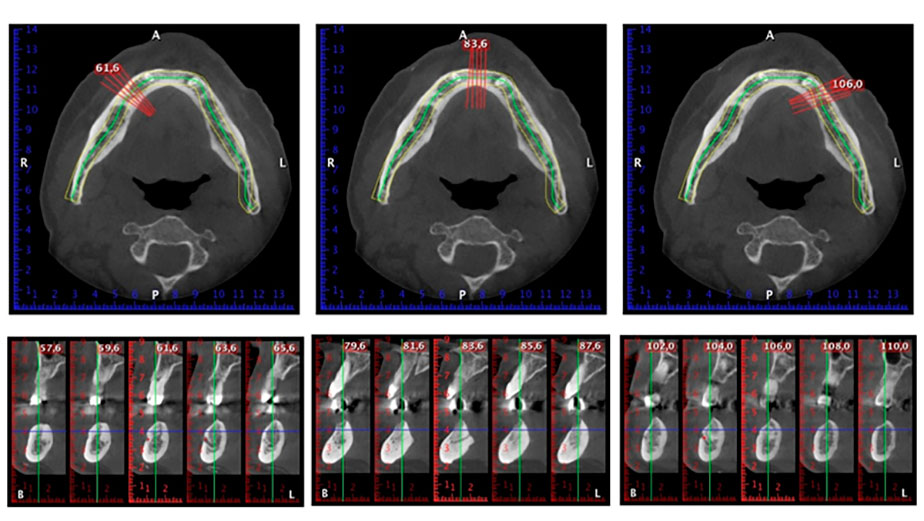

È stata eseguita una tomografia computerizzata Dentale Cone Beam in 3D (CBCT, con Planmeca) per aiutare la programmazione dell'intervento e la riduzione di rischi. L'esame ha evidenziato che la qualità e quantità dell'osso disponibile era sufficiente per eseguire l'intervento e la ricostruzione immediata, utilizzando il metodo Fast & Fixed. In base al protocollo del sistema, gli impianti sono stati inseriti in posizione 35, 32, 42 e 45. Gli impianti distali vengono installati a un angolo massimo di 45 gradi. Così facendo, il profilo che ne risulta viene spostato in posizione posteriore, generando un poligono di supporto più ampio (Fig. 3).